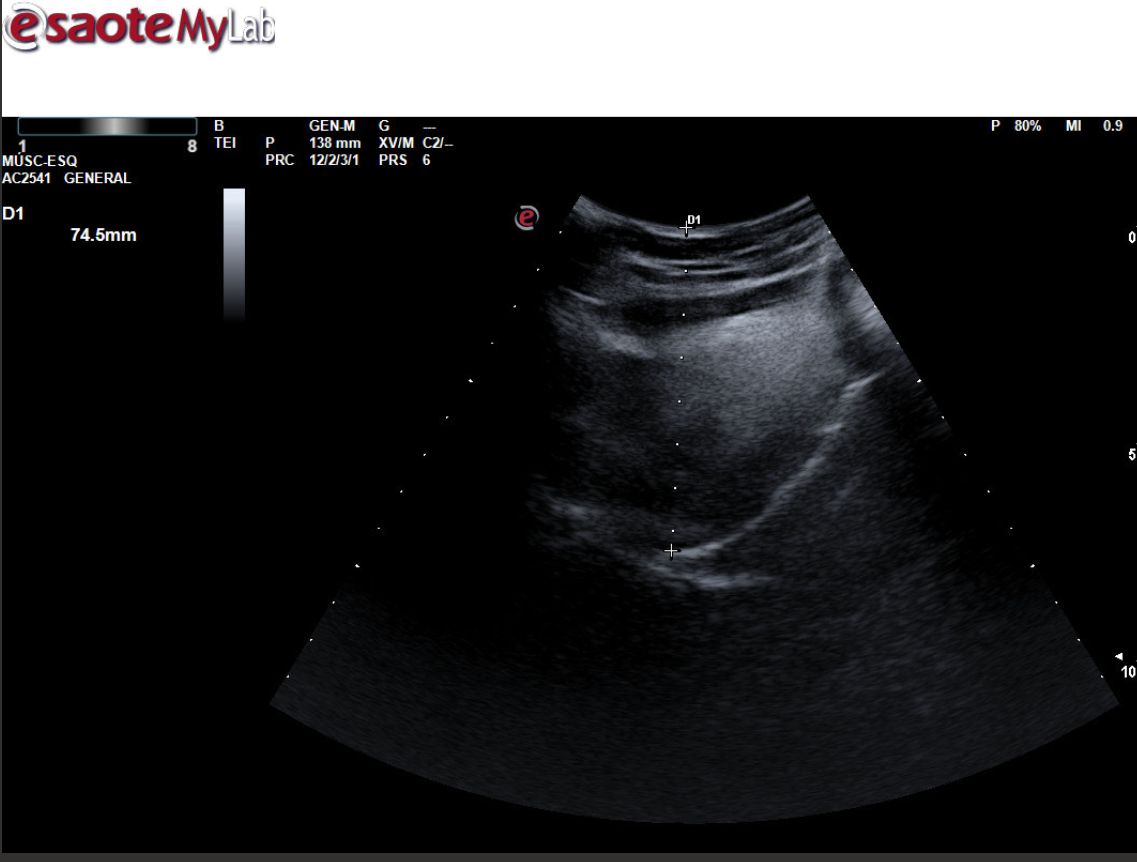

Para ello ponemos en práctica el protocolo específico de detección ecográfica de AOS, mediante la medición de la base de lengua y del espacio retrofaríngeo posterior para ver si cumple los criterios ecográficos establecidos, con las mediciones correspondientes que establecen la sospecha.

Buscar correlación entre los hallazgos encontrados y el diagnóstico de SAOS, esto nos ayuda a confirmar si la realización de esta valoración ecográfica nos ayuda a discernir si un paciente sintomático es más susceptible a ser derivado para estudio o no, especialmente en pacientes con duda clínica.